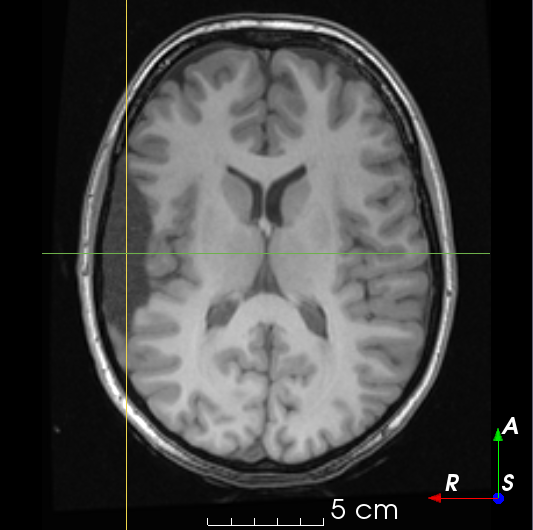

Refer to caption

(a)

(b)

(c)

(d)

(e)

(f)

(g)

(h)

(i)

(j)

Figure 5: Resection simulations 𝑿Rsubscript𝑿𝑅\bm{X}_{R} generated using our method.